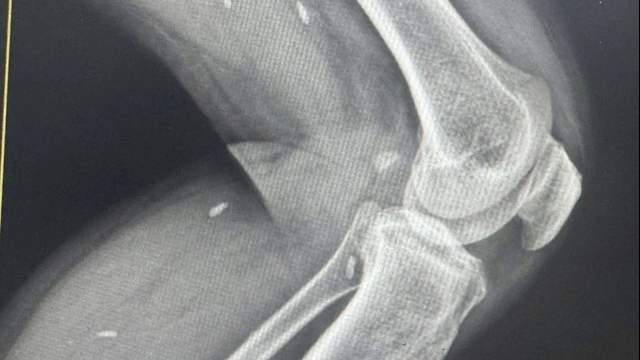

Các bác sĩ khoa Ngoại Tổng hợp đã quyết định phẫu thuật thám sát, xử trí tổn thương, phát hiện có 2 dị vật gây tắc ruột hoàn toàn. Ê kíp đã lấy ra 2 dị vật dạng trái cây (giống trái chà là) kích thước 4x2cm, khâu lại ruột, dẫn lưu theo dõi.